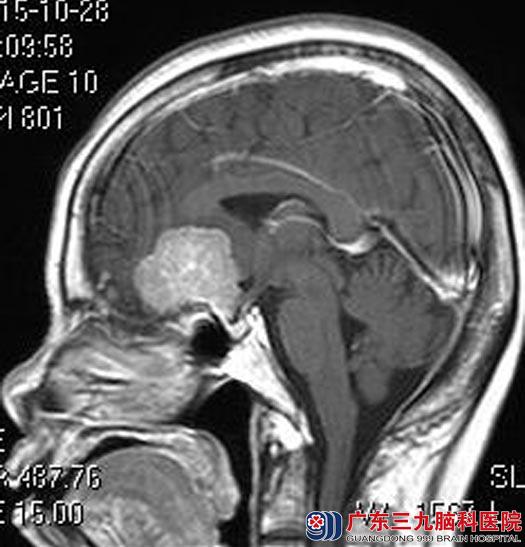

广东三九脑科医院头颅MR检查显示:前颅底左侧鞍结节示类圆形宽基底生长占位病灶,33.9mm×40.6mm×28mm,考虑脑膜瘤,病变血供较丰富,左侧颈内动脉海绵窦段小动脉瘤。